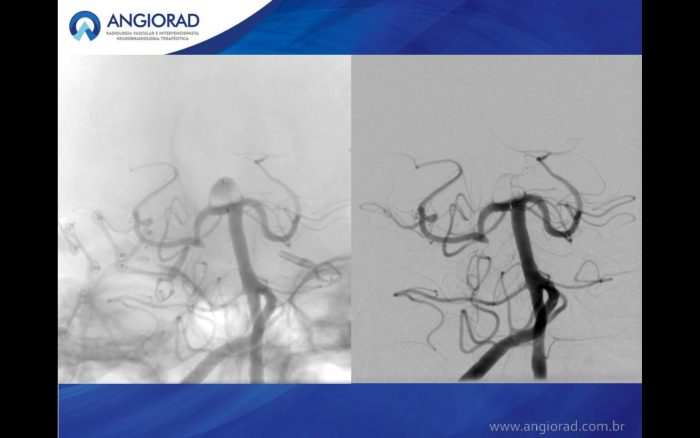

A interrupção do fluxo do aneurisma com o dispositivo WEB (Woven EndoBridge – Microvention Terumo) é uma abordagem endovascular inovadora para o tratamento de aneurismas de bifurcação de colo largo. Estudos iniciais mostraram uma baixa taxa de complicações com boa eficácia.

WEB é um tratamento intrasacular inovador para aneurismas intracranianos. Séries preliminares mostraram boa segurança e eficácia. O WEBCAST é um estudo europeu prospectivo que avaliou a segurança e eficácia do dispositivo em aneurismas de bifurcação de pescoço largo. O estudo demosntoru segurança a curto prazo do tratamento dos aneurisma com WEB e bons resultados anatômicos após 6 meses.

A população acumulada foi composta por 168 pacientes com 169 aneurismas, incluindo 112 indivíduos do sexo feminino (66,7%). A idade dos pacientes variou entre 27 e 77 anos (média de 55,5 ± 10,2 anos). As localizações dos aneurismas eram artéria cerebral média em 86/169 aneurismas (50,9%), artéria comunicante anterior em 36/169 (21,3%), artéria basilar em 30/169 (17,8%) e terminal da artéria carótida interna em 17/169 (10,1 %) O aneurisma foi rompido em 14/169 (8,3%). Não houve mortalidade em 1 mês e a morbidade relacionada ao procedimento / dispositivo foi de 1,2% (2/168). Em 1 ano, oclusão completa do aneurisma foi observada em 81/153 aneurismas (52,9%), remanescente do pescoço em 40/153 aneurismas (26,1%) e remanescente do aneurisma em 32/153 aneurismas (20,9%). O re-tratamento foi realizado em 6,9%.

Estas séries mostram a alta segurança e boa eficácia a médio prazo deste tratamento.